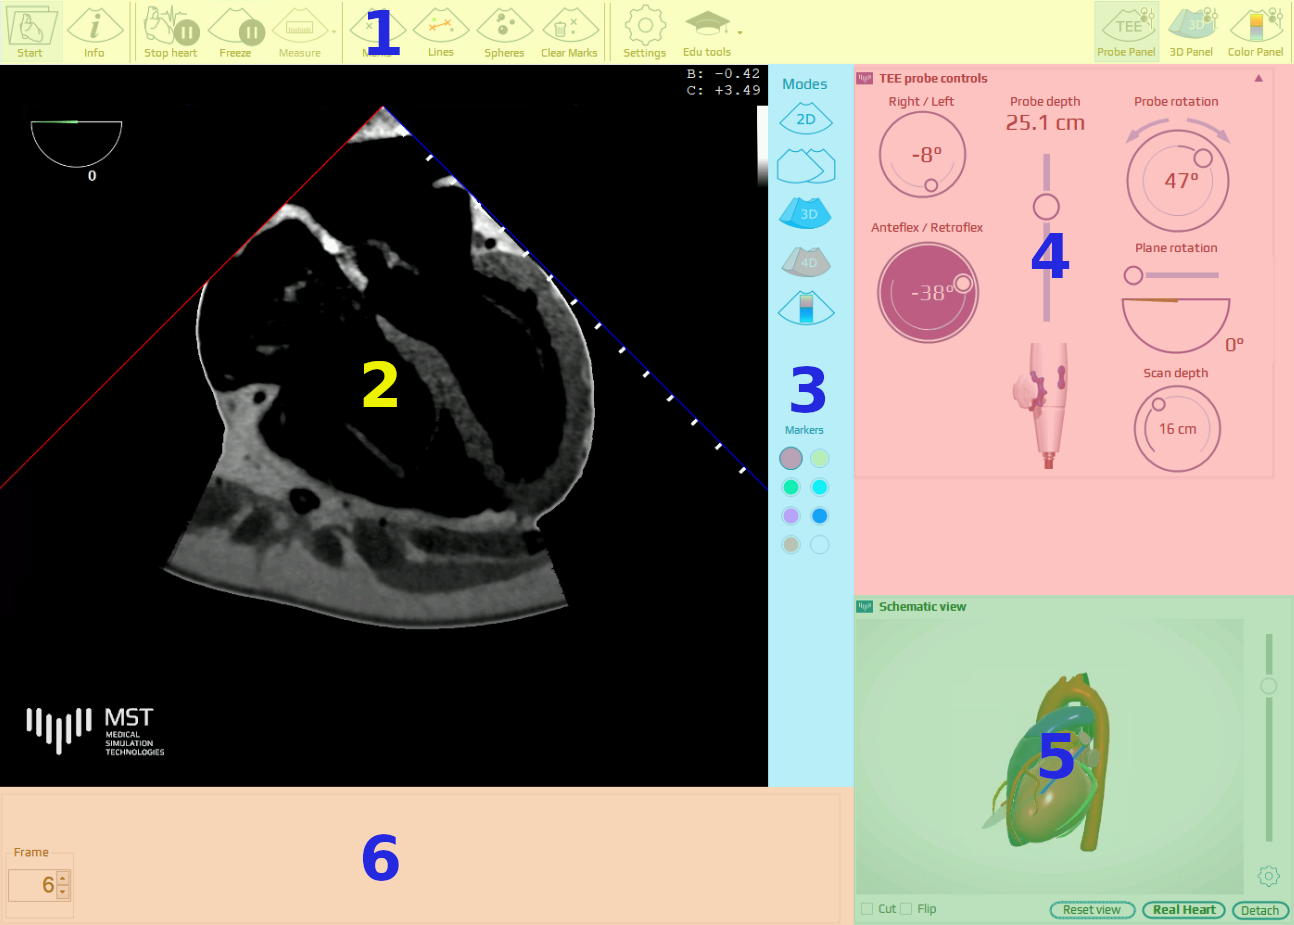

The simulation screen

The user interface window layout has 6 main sections: Top main menu (1), TEE sector view (2), modes panel (3), TEE probe control panel (4), heart visualization sector (5) and the bottom bar (6).

TEE control panel

The TEE control panel shows the position and orientation of the TEE probe and imaging plane. Using a mouse the User can change each of the manipulators settings. It can be manipulated by dragging or using the mouse scroll wheel when the coursor is on the given control. Hover over any of the manipulators to see its function.

Right-left flexion of the probe tip (RIGHT / LEFT angle given in degrees)

Probe depth in the esophagus. SCAN DEPTH indicator shows the depth of scanning in cm

Rotation of the probe in the esophagus (clockwise/counterclockwise rotation given in degrees, related to anterior orientation

Anterior – posterior flexion of the probe tip (ANTEFLEX / RETROFLEX angle given in degrees)

TEE omniplane rotation angle given in degrees

Scan depth, can be changed with a mouse

Below the TEE panel, the animated model of the heart with superimposed TEE imaging plane is displayed. The model can be rotated with the mouse and enlarged using the mouse wheel. The panel can be detached from the original position, moved with the mouse to the desired location on the screen and resized by dragging the edge/corner of the window. By clicking CUT the section of the model corresponding to the TEE plane orientation can be displayed. Clicking FLIP causes display of the opposite part of the section.